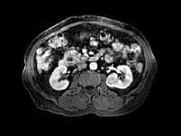

- 多项选择题男,67岁, 无痛性血尿1月,IVP和MRI检查如图示, 下列说法正确的是 ( )

B、左肾中部内侧可见类圆形不均匀信号肿块突向外

C、左肾上极可见一T

WI为高信号圆形病灶,边界清楚D、左肾中部病灶考虑为小肾癌

E、左肾上极病灶考虑为肾囊肿